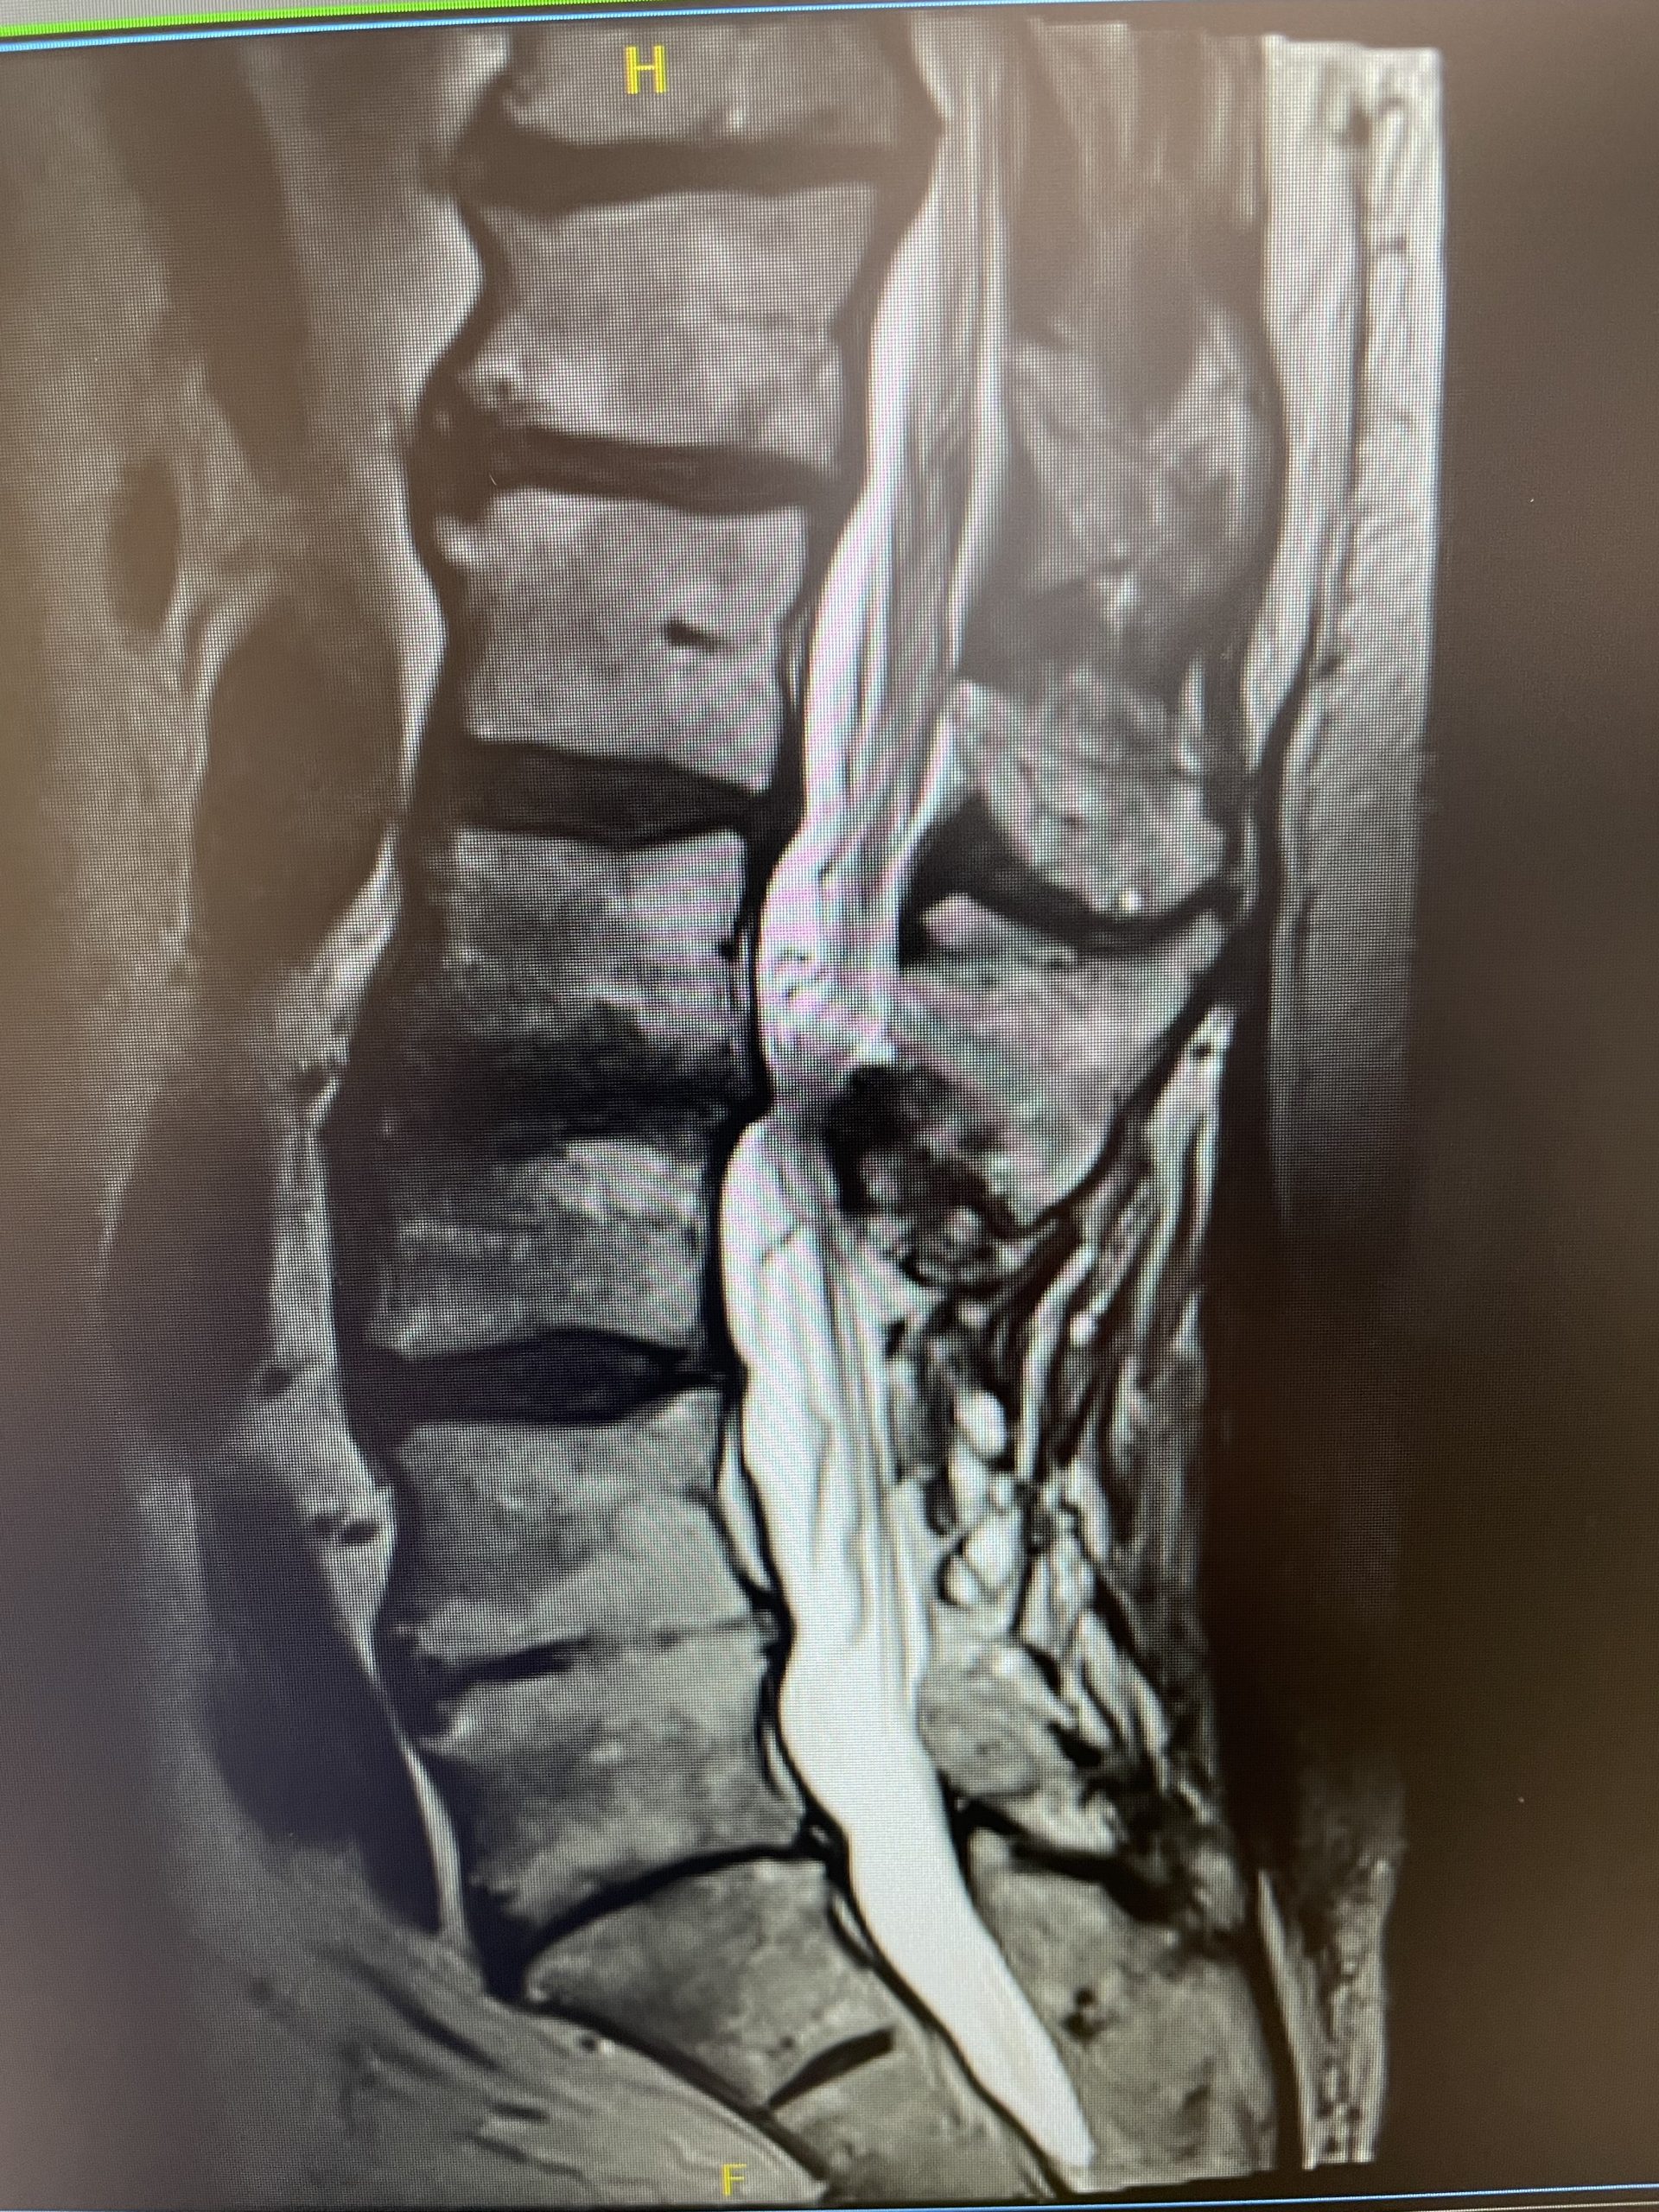

This 52 year-old female presents with 4 months of progressive neck pain, numbness of both hands, and difficulty using her hands and buttoning a shirt. She was noted to have mild right-sided weakness in a long track distribution which included her finger extensor, hip flexor, dorsiflexor weakness. She had tried chiropractic care. Imaging revealed a very large C4-5 disc herniation with severe cord compression which was more eccentric to the right, but also causing left-sided compression (Fig 1). The patient also had C5-6 disc collapse with biomechanical reduction of the C5-6 motion segment which puts more stress on the next segment. In essence the C5-6 is acting like it is autofused. This resulted in premature degeneration of the C4-5 segment which resulted in the disc herniation. It was decided, given a diagnosis of early cervical myelopathy with spinal cord compression, to offer an anterior cervical discectomy and fusion at C4-5 to decompress the spinal cord.